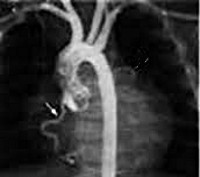

Наиболее точные сведения в отношении синдрома Бланда-Уайта-Гарланда дают аортография и селективная коронарография (КТ-коронарография, МСКТ-коронарография). При этом на ангиограммах визуализируется разветвленная правая и аномально расположенная левая коронарные артерии, ретроградный сброс контраста в легочный ствол.